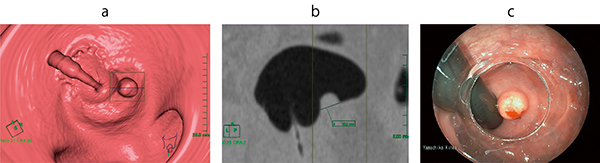

ポリープなど病変が疑われる場合は,ポリープ観察ツールで病変の直交断面を2D画像ですぐに見ることができ,計側にも大変便利である(図3)。

図3 ポリープ(直腸カルチノイド)の計測

a:仮想内視鏡画像でのポリープ観察ツール使用時

b:ポリープ観察ツールでの直交断面画像(大きさ10.2mm,CT値44HU)

c:同部位の内視鏡画像